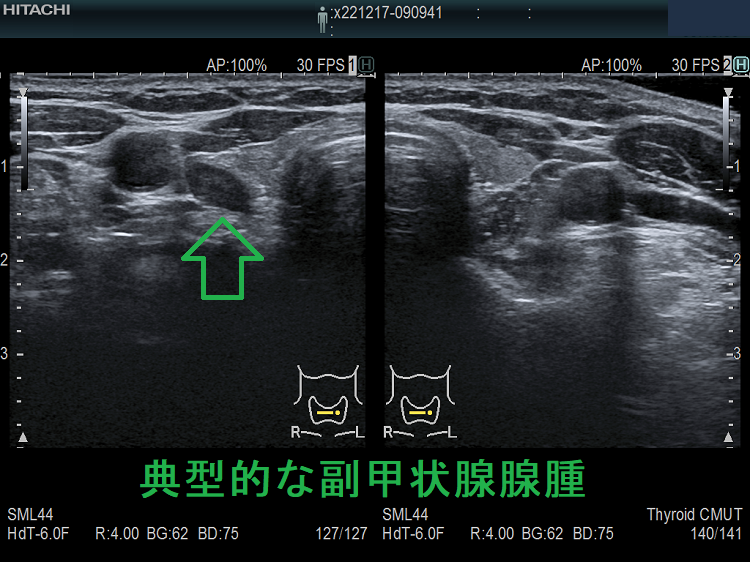

(➸)原因となる副甲状腺腺腫、副甲状腺癌、副甲状腺過形成をデジタルハイビジョン超音波診断装置で診断。エコーでは、甲状腺とのインピーダンスの違いにより、甲状腺-副甲状腺境界部に線状高エコーが生じます(右図の↓)。内部は中心血流を認め、リンパ節でないのが分かります。

甲状腺内副甲状腺腫は、超音波(エコー)検査で甲状腺腫瘍と形態的に鑑別できない場合があります(実際は下の写真のように診断できていますが・・)。特徴的な超音波(エコー)所見は、腹側の高エコーで感度86%、特異度100%です[Surgery. 2012 Dec;152(6):1193-200.]。さらに、99m-Tc MIBIシンチグラフィーで取り込み(集積)があれば甲状腺内副甲状腺腫と診断できます。